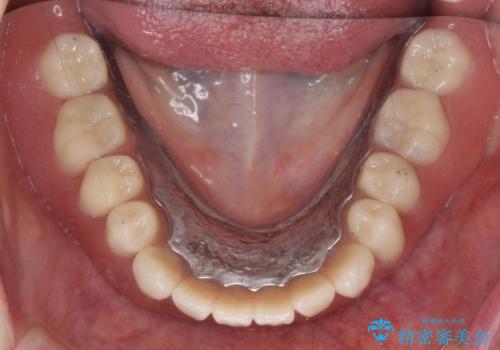

セラミック・インプラント治療を含む包括歯周病治療

できる限り口の中を綺麗にしたい。